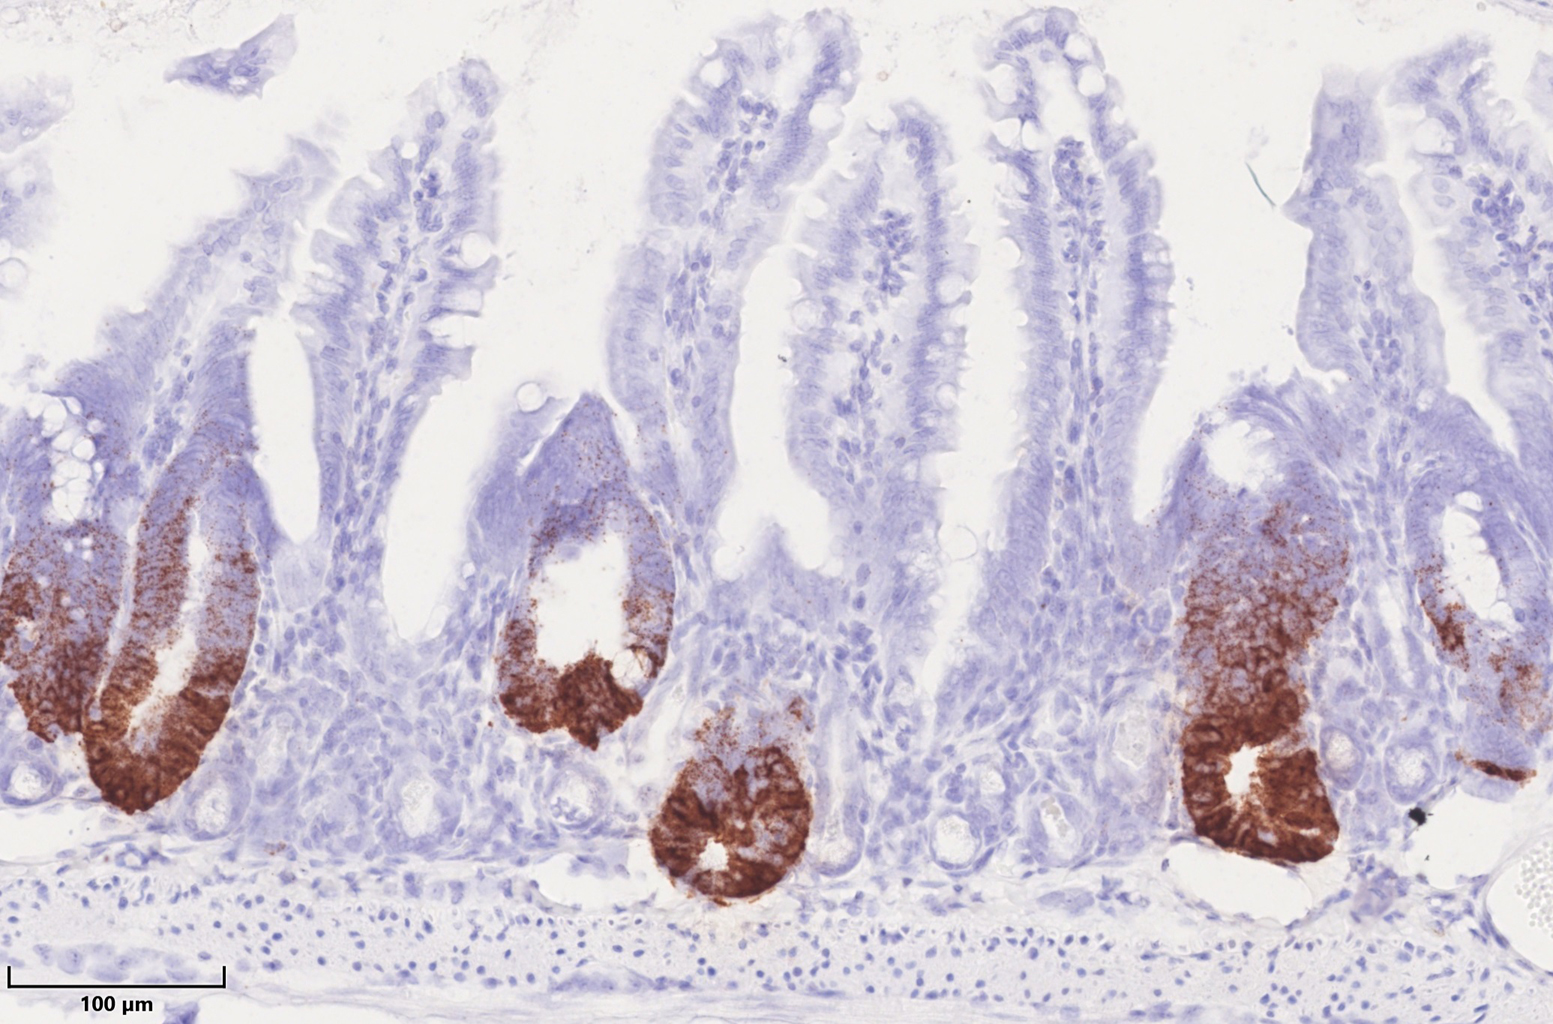

HSP60 in Mitochondrien kontrolliert die Stammzellproliferation im Darmepithel. HSP60-negative Krypten im Darm zeichnen sich durch den Verlust von braungefärbten Stammzellen aus, während HSP60-positive Darmareale eine verstärkte Stammzellproliferation zeigen. (Foto: Team Haller/ TUM)

Auf der einen Seite war die Atemkapazität und der zelluläre ATP-Spiegel reduziert, beides Schlüsselaufgaben des Mitochondriums, dem Powerhaus der Zelle. Daneben konnten Professor Haller und sein Team beobachten, dass alle Zellen ohne HSP60 Veränderungen aufzeigten. Stammzellen verloren ihre Fähigkeit zur Selbsterneuerung, während umliegende Epithelzellen ein Wachstumsprogramm initialisierten.